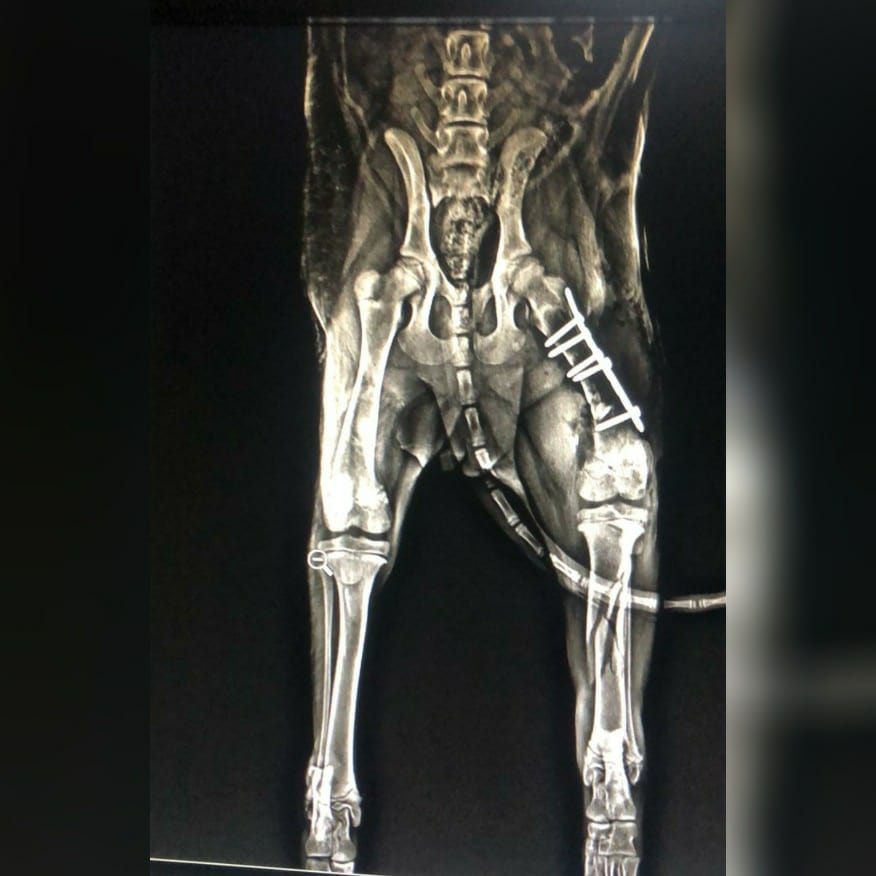

Our baby girl Maple had her surgery yesterday. She has had a plate inserted in her hip joint (slide 3)and the other two breaks have been aligned and plastered.